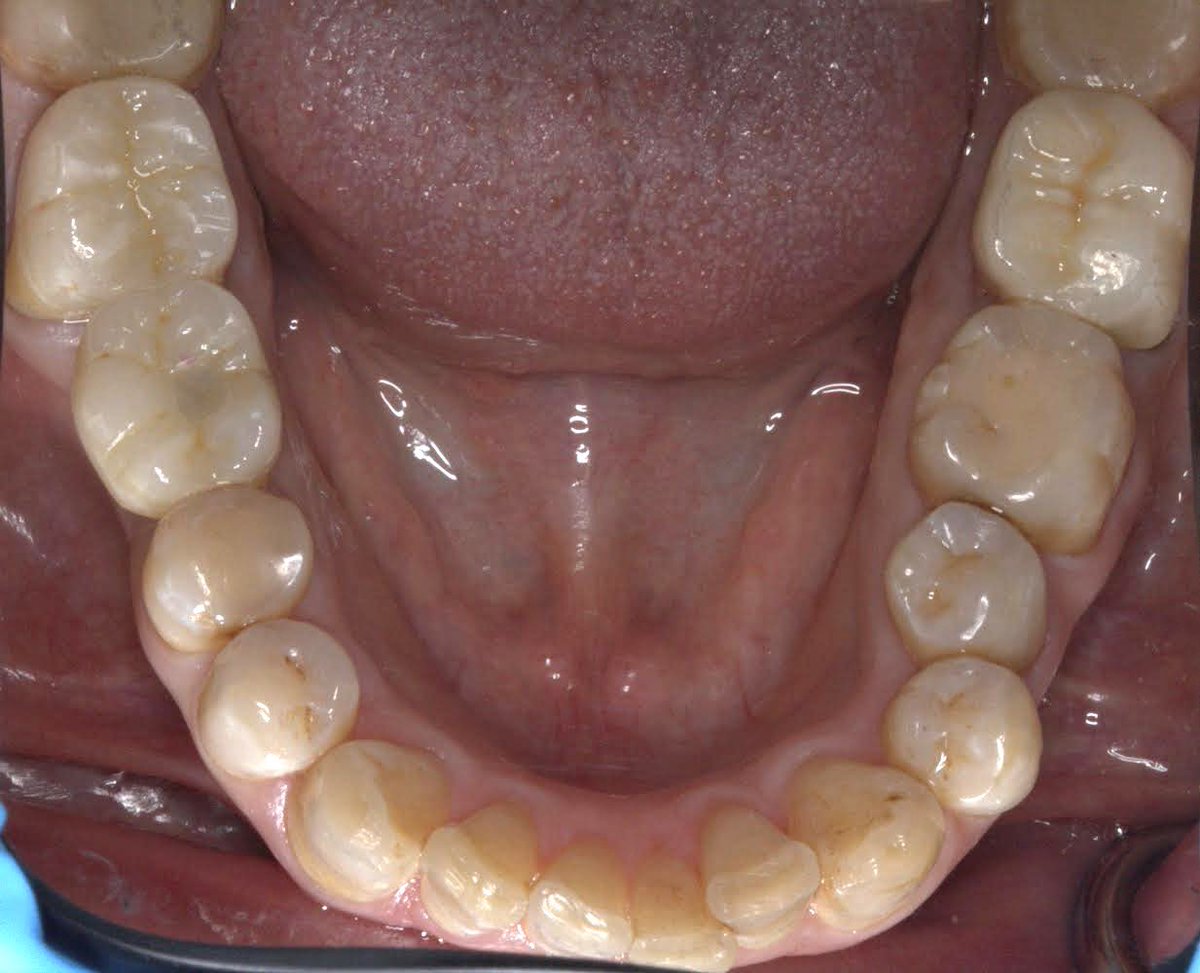

Zirconia crown on Endotreated #47 Implant supported crown on #46, The implant was placed by @alomar_ahmed